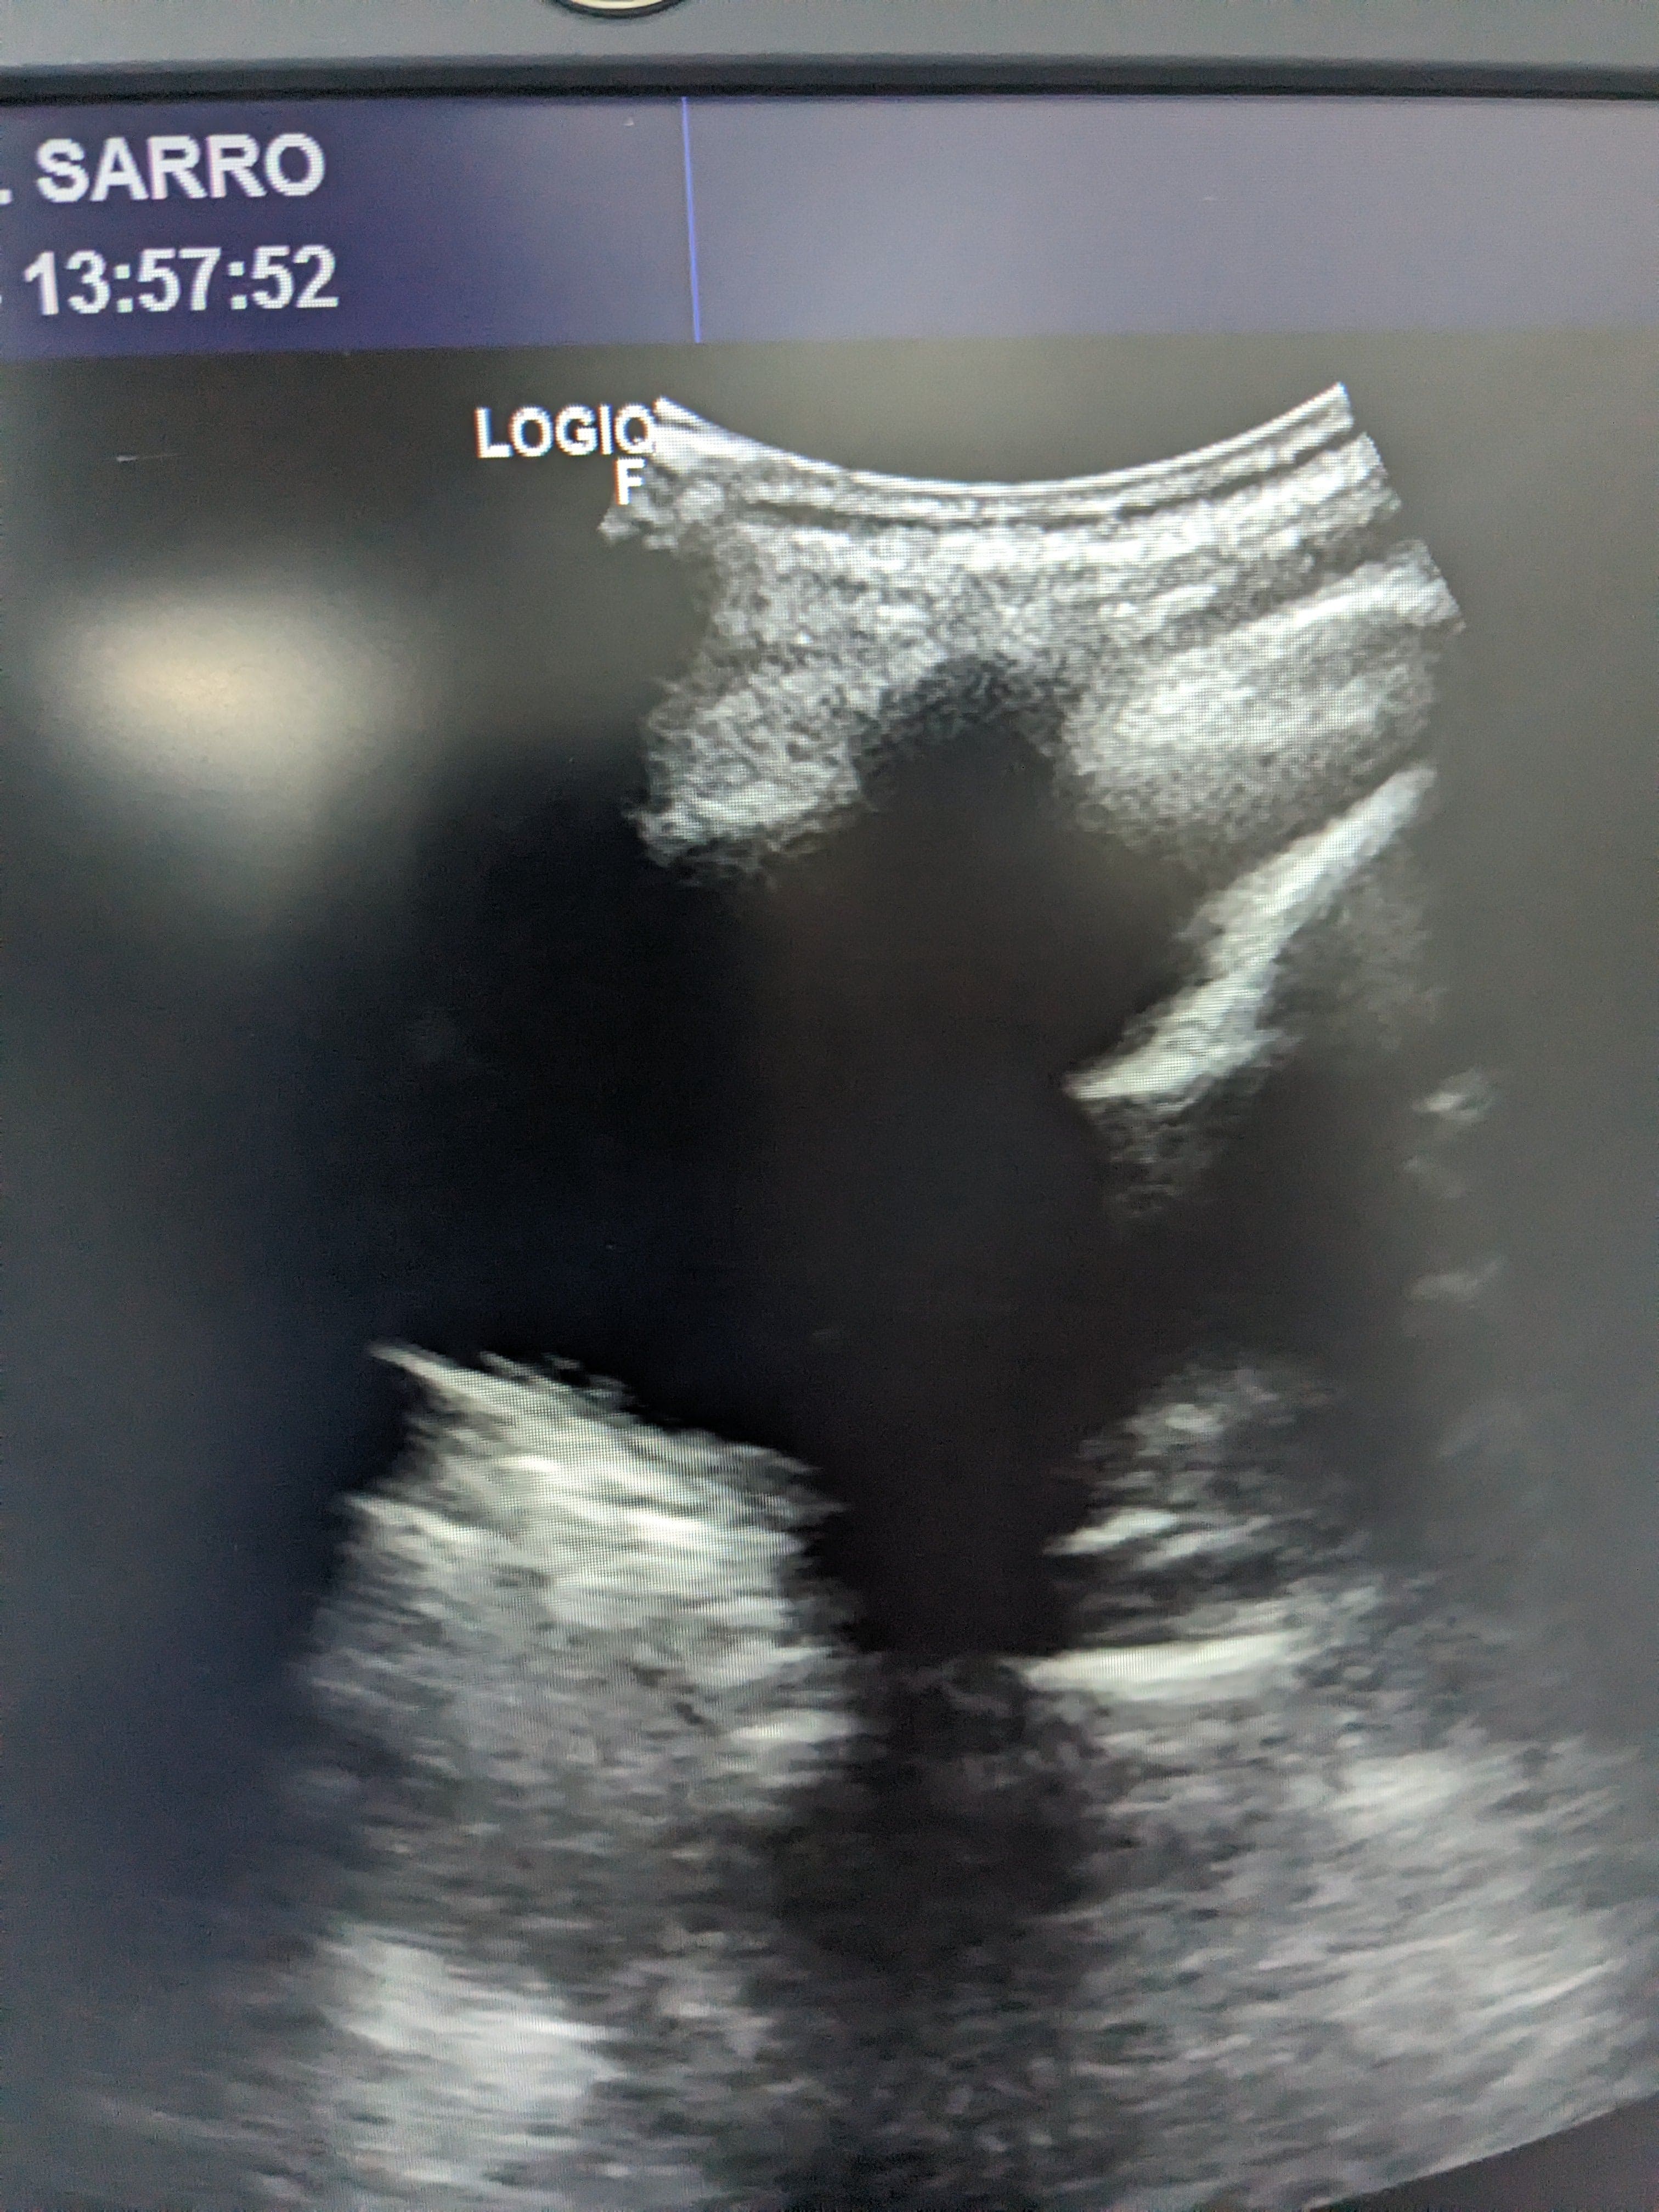

Se hace ecografía clinica en la consulta de atención primaria, observamos derrame pleural en pulmón izquierdo hasta medio campo pulmonar.

Se orienta como derrame pleural de origen desconocido por lo que se deriva a urgnecias del hospital de referencia para valoración de pruebas complementarias y tratamiento.

Rx torax: derrame pleural izquierdo. Sin pinzamiento de seno derecho. Sin infiltrados ni condensaciones.